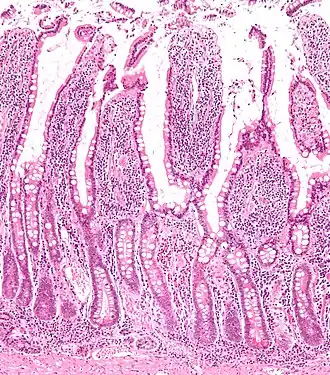

Microscopische vergroting die de darmvlokken in het dunnedarmslijmvlies laat zien met de darmvlokken en crypten van Lieberkühn.

Darmvlokken[1] ofwel villi intestinales[1] (enkelvoud villus intestinalis) zijn de vlokkige aanhangsels in de darmen (vooral in de dunne darm). Er zijn villi en microvilli.

Werking van de darmvlokken